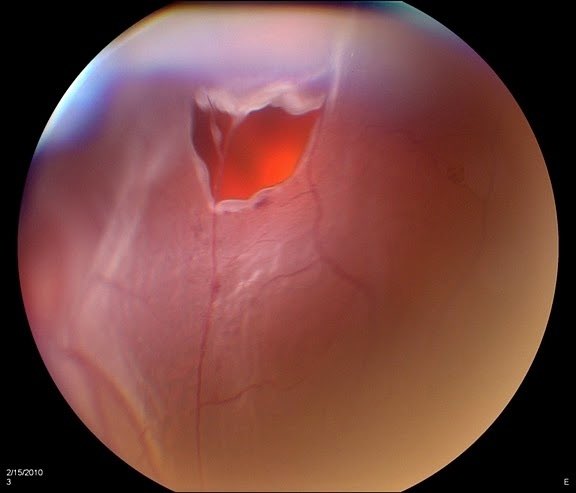

٣. نزيف السائل الزجاجي

العلاج: حسب المسبب وقد يشمل

- مراقبة قريبة

- ليزر للشبكية

- حقن للشبكية

- جراحة شبكية